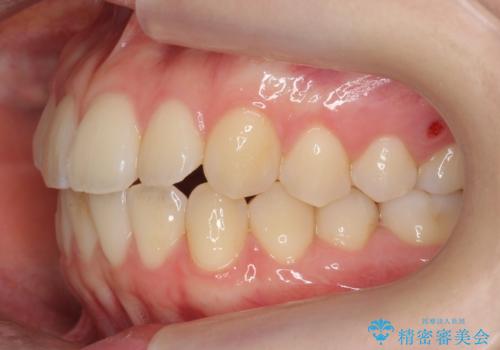

下の八重歯 歯を抜かずに インビザライン治療

途中患者様のご都合で治療を中断していたため、長くかかっていますが、実質2年程度で終わる内容でした。